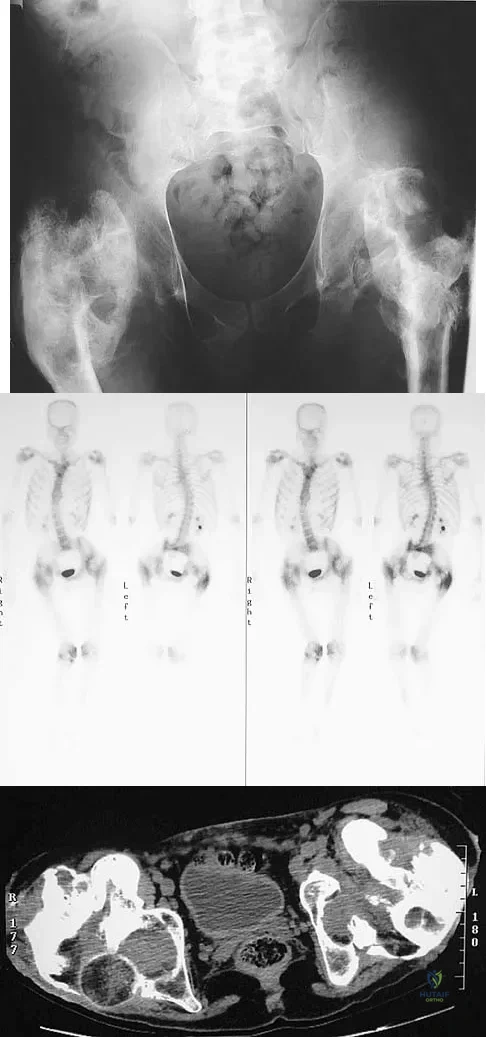

Figure 11a shows the AP pelvis radiograph of a 25-year-old man who sustained a spinal cord injury 10 years ago. A bone scan and a CT scan are shown in Figures 11b and 11c. To prevent recurrence after resection, management should consist of